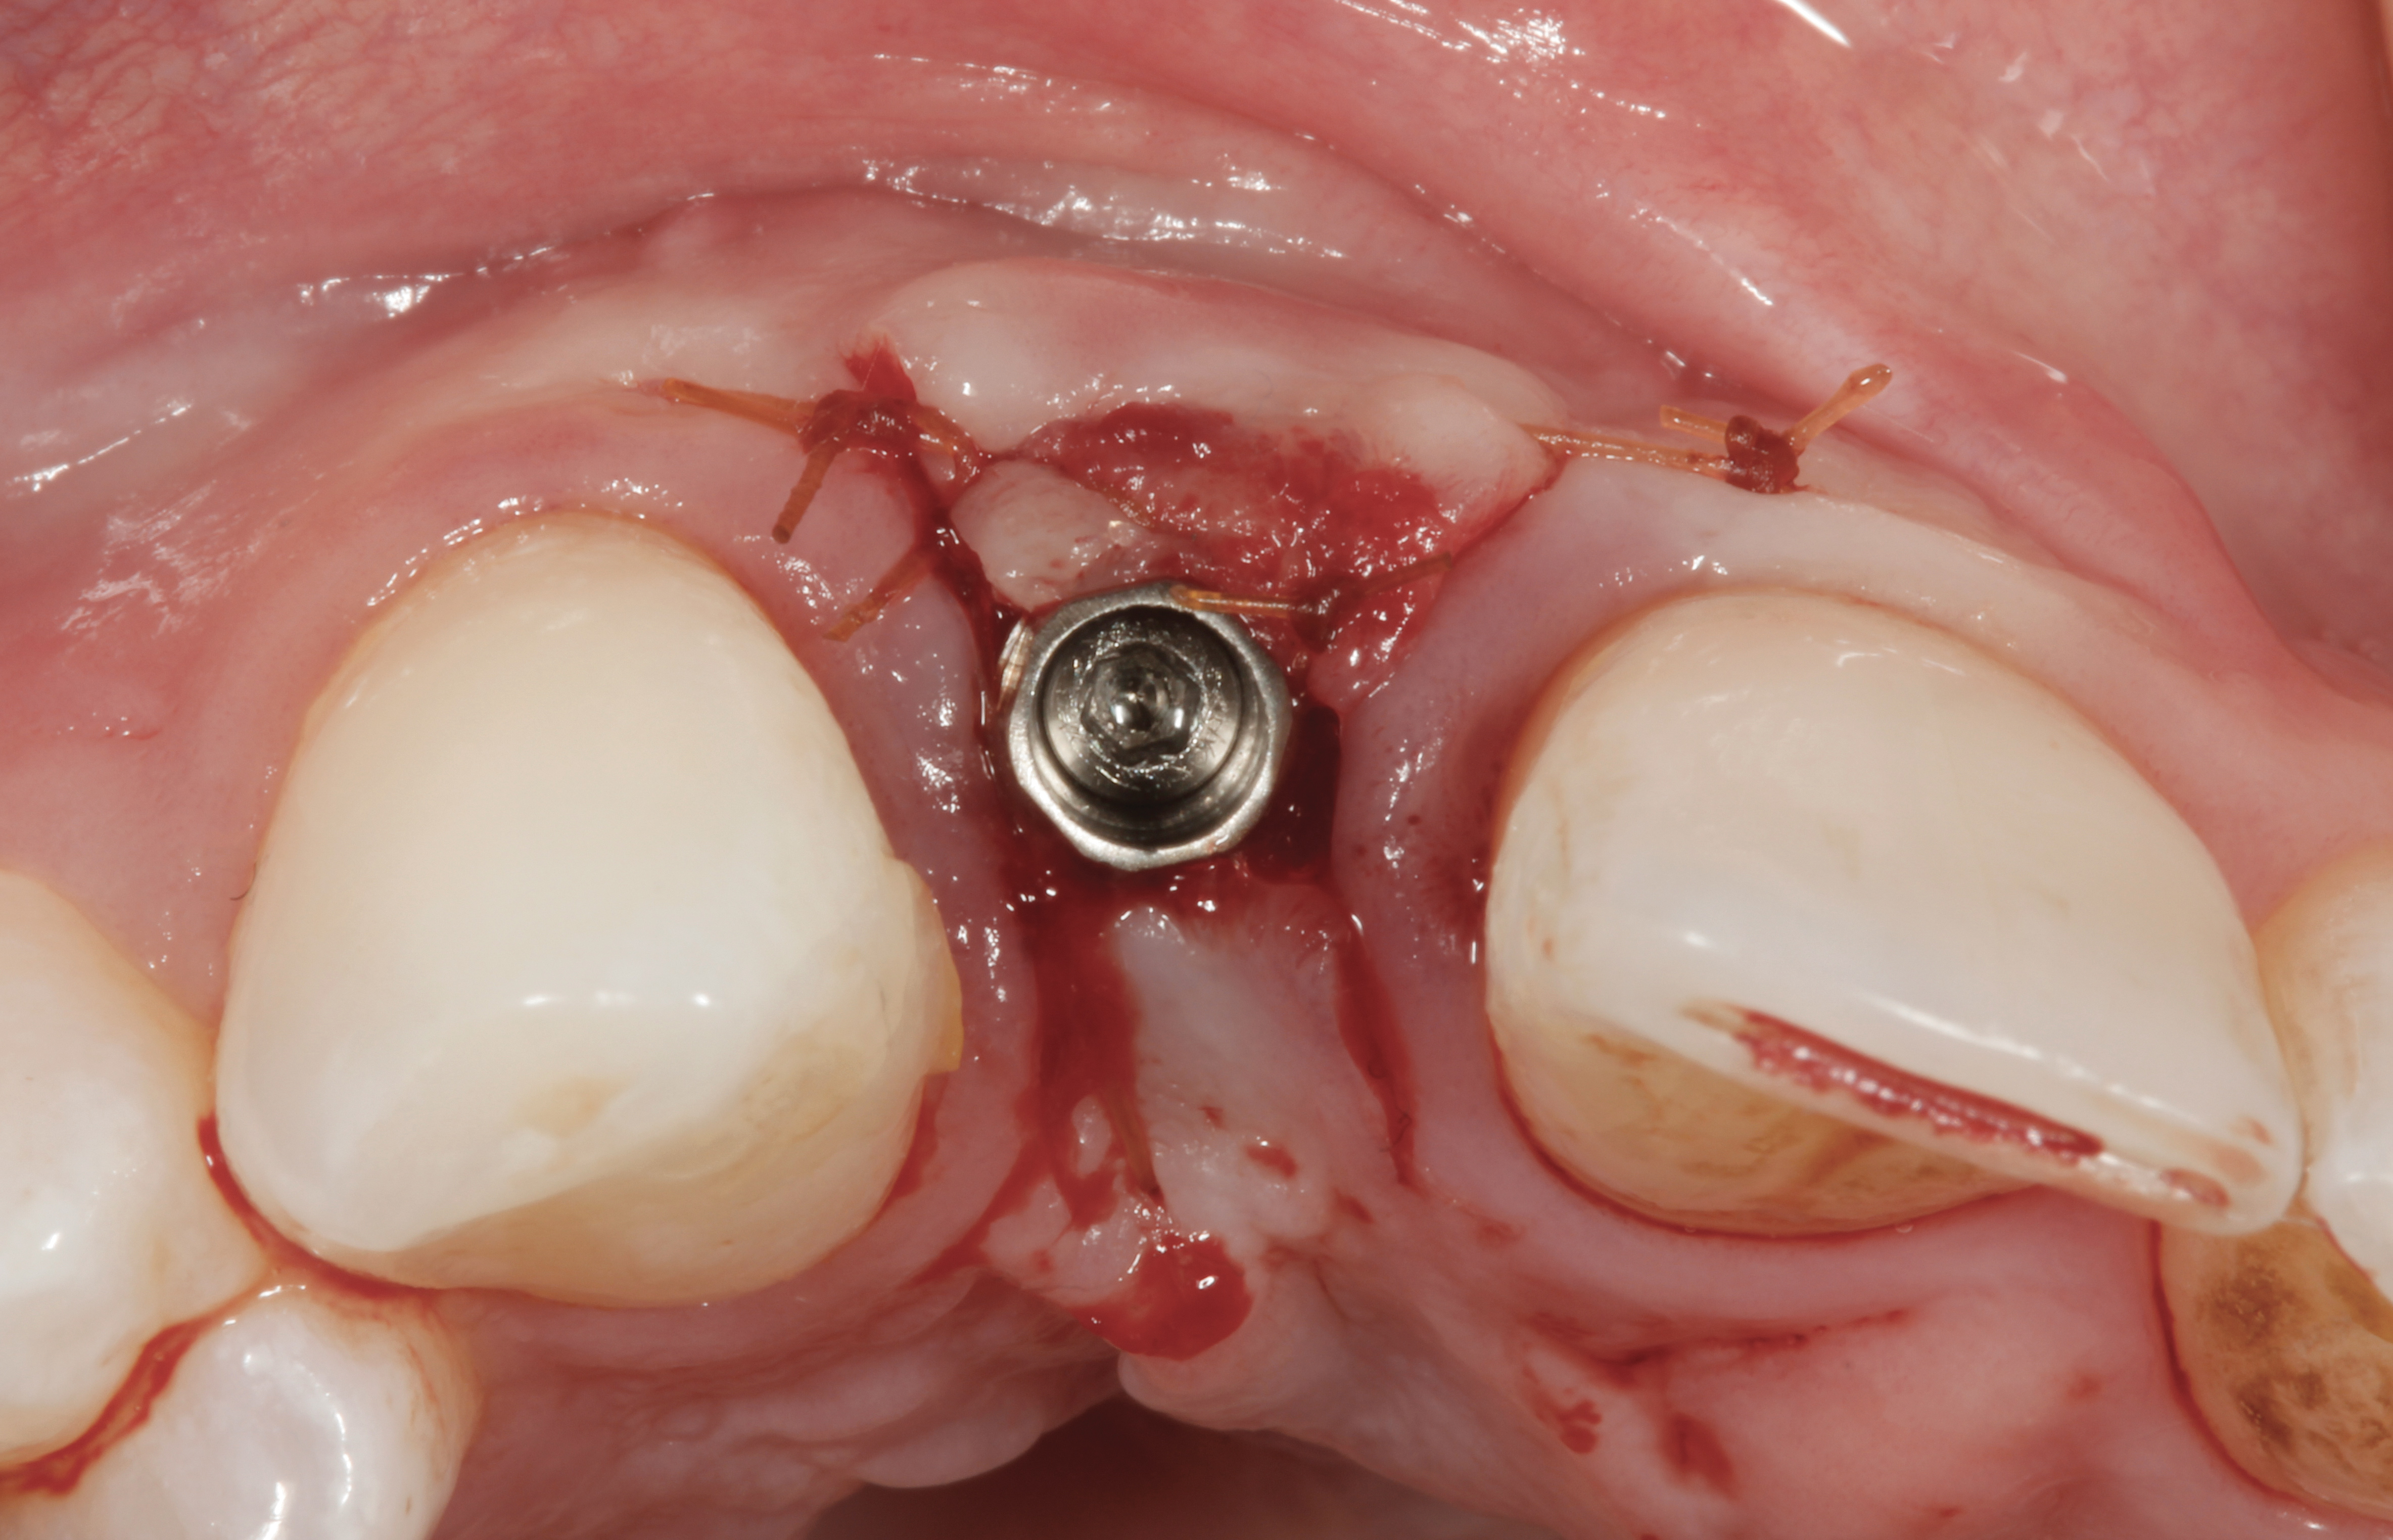

The crown and screw-retained custom abutment were removed, and a surgical cover screw was placed into the implant, thereby allowing spontaneous gingival augmentation in situ (Figure 33 and Figure 34). Note that the lingual aspect of the implant site was significantly more coronal than the labial aspect, which was positive because the defect would be limited to a facial–lingual defect. A fixed RBR bridge was cemented on the adjacent teeth and used as a tooth-supported transitional provisional restoration (Figure 35). A few weeks were allotted to let the soft tissue heal and migrate around the cover screw (Figure 36) to see if there would be complete coverage, thereby allowing a soft-tissue augmentation procedure to be performed with primary flap closure as in clinical scenario No. 2. The major obstacle in achieving a positive tissue response was that the implant depth was also deficient because the implant–abutment connection was at the level of the free gingival margin. It was decided that the best treatment option would be to remove the implant. A high-powered reverse-torque device (Fixture Remover Kit, NeoBiotech, www.neobiotechus.com) was used to remove the implant atraumatically (Figure 38 through Figure 41). The implant socket was allowed to heal for several months not unlike an extracted tooth (Figure 42). A new implant was placed in a better position from both a restorative and esthetic perspective (Figure 43), and after a few months of healing, a new crown was made (Figure 44). A satisfactory functional and esthetic result was achieved (Figure 45 and Figure 46) without employing pink porcelain.

Fig 43. A full thickness flap was raised to place a new 3.25-mm implant into tooth No. 26 area in a single-stage protocol.

Fig 38. A reverse-torque screw was placed into the implant.

Fig 39. A counter-torque device was placed over the reverse-torque screw.

Fig 40. The implant was easily unscrewed within minutes in a minimally invasive manner with less trauma to the surgical site.